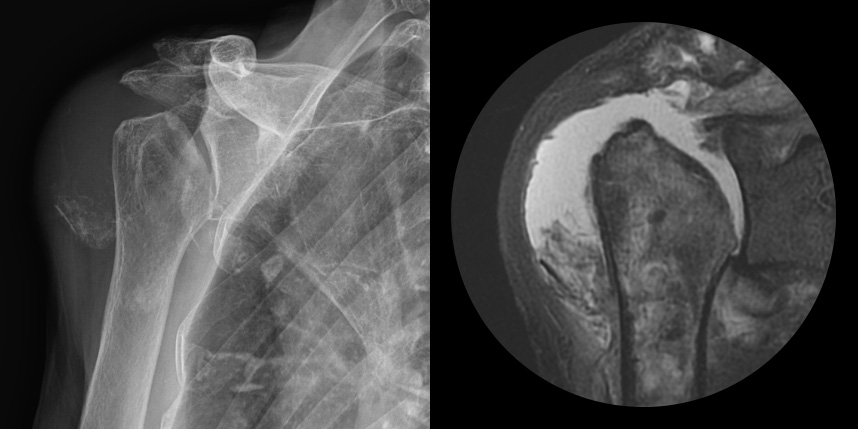

회전근개 파열의 크기가

매우 큰 경우

어깨 퇴행성은 많이 써서 닳고 노화에 따른 변화가 생긴 것으로, 말 그대로 어깨가 많이 사용되면서 연골이 닳아서

마모돼어 생기는 관절염입니다. 어깨 회전근개 관절병증 원인으로는 어깨 힘줄 파열을 방치했을 때 관절이 틀어진 상태에서 계속

사용하게 되면 관절이 많이 상해서 관절염까지 진행되며, 이런 경우 회전근개파열의 결과로 생긴 관절병이라고 합니다.